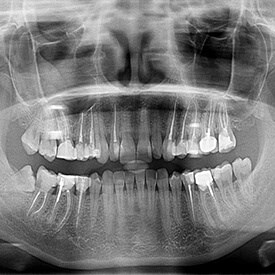

Our team at Zensmiles strives to stand out from our peers in many ways. One of these ways is by offering metal-free options to patients of all ages to further the health and beauty of their smile. In the past, cavities were filled with amalgam filling that contained mercury and other dangerous metals. While we didn't realize how serious these substances were in the past, we now have the knowledge and technology to ensure that we use safe, proven methods to preserve the integrity of your teeth. Board-certified dentist Dr. Mohit Shardha stays ahead of the curve by offering metal-free dentistry at our office in Frisco, TX. To learn more about metal-free dentistry or to schedule your appointment, get in touch with our office today!

If you currently have a cavity or have had tooth decay sealed off in the past with amalgam fillings, you might be an ideal candidate for metal-free dentistry. During your appointment, Dr. Shardha or a member of his team will thoroughly evaluate your oral health and look for signs of cavities or the breakdown of older fillings. Once we've assessed the condition of your teeth, we will craft a personalized, metal-free treatment plan to fix your cavity and address your needs.